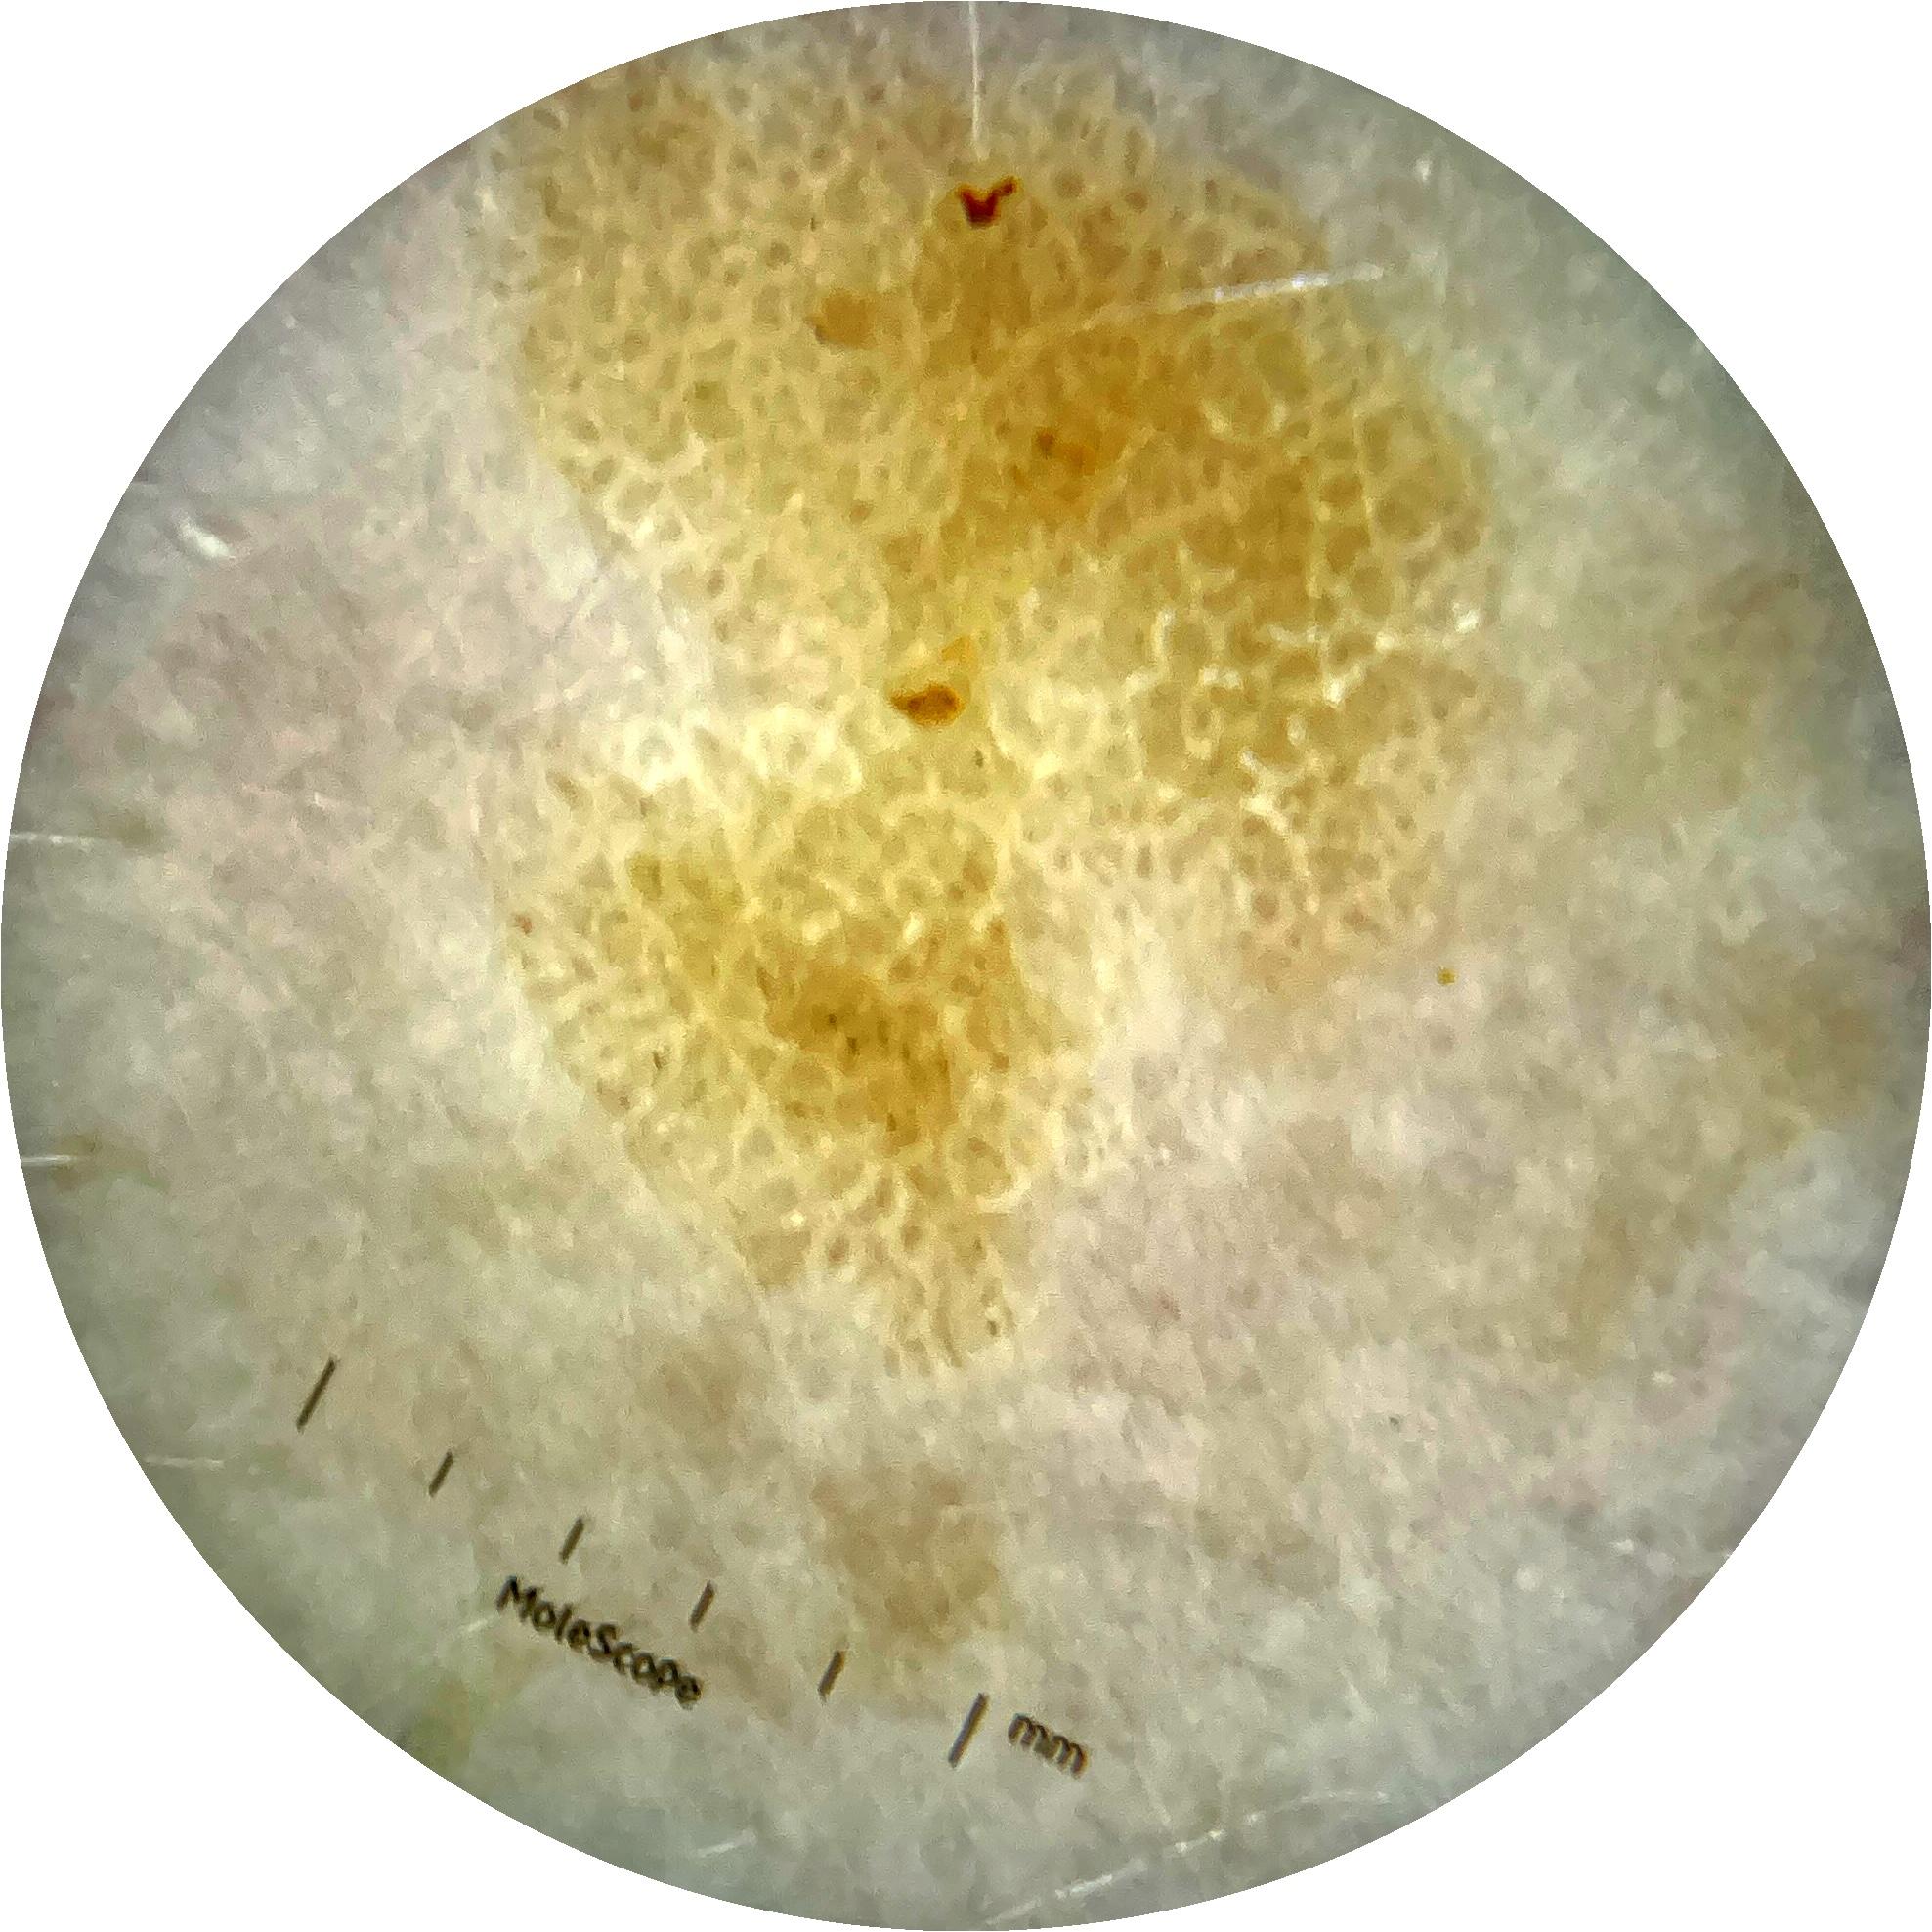

ISIC_9785574

2003 x 2003

Clinical

Field Value

acquisition_day 148

age_approx 45

anatom_site_1 Head and neck

anatom_site_general head/neck

diagnosis_1 Benign

diagnosis_confirm_type single image expert consensus

image_type dermoscopic